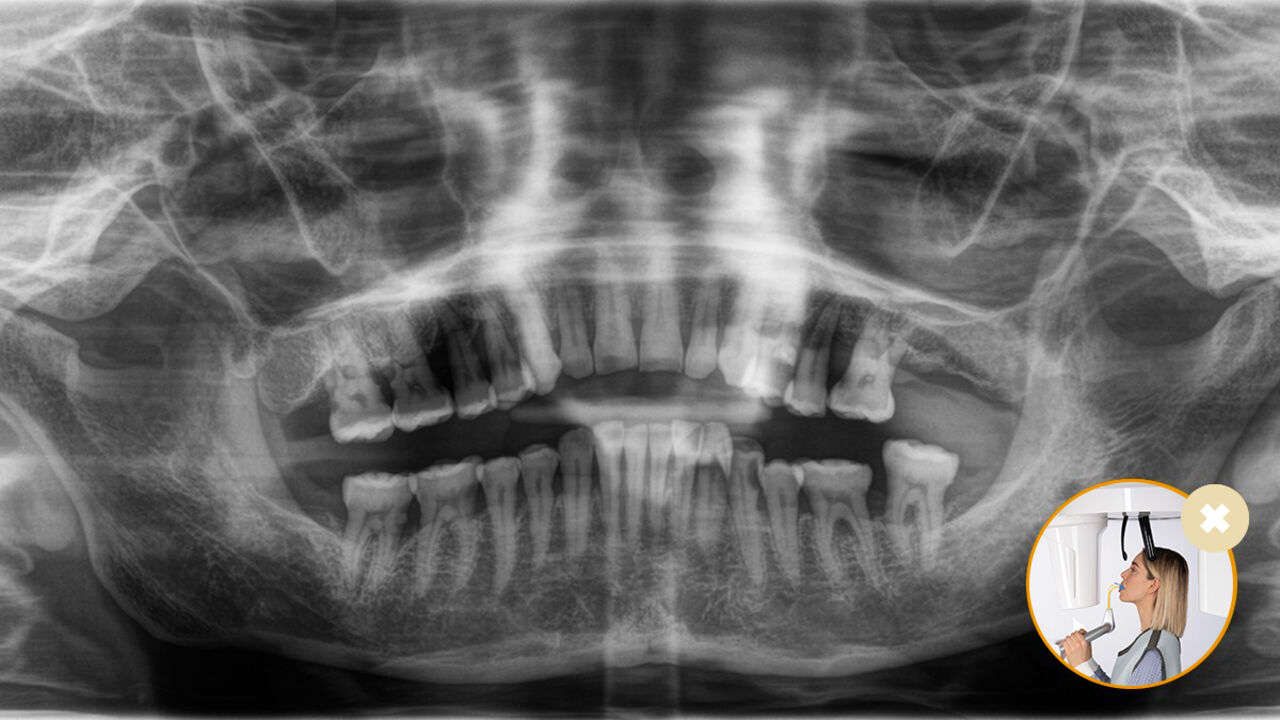

El posicionamiento correcto del paciente permite obtener imágenes de alta calidad que respaldan un diagnóstico preciso y facilitan y mejoran la experiencia del paciente.

Este es nuestro concepto de 10 puntos para facilitar el posicionamiento del paciente y la obtención de imágenes radiológicas. Se trata principalmente de dos cosas: alta calidad de imagen y comodidad para el paciente y el asistente.

El resultado: Escaneos precisos gracias al bloque de mordida oclusal